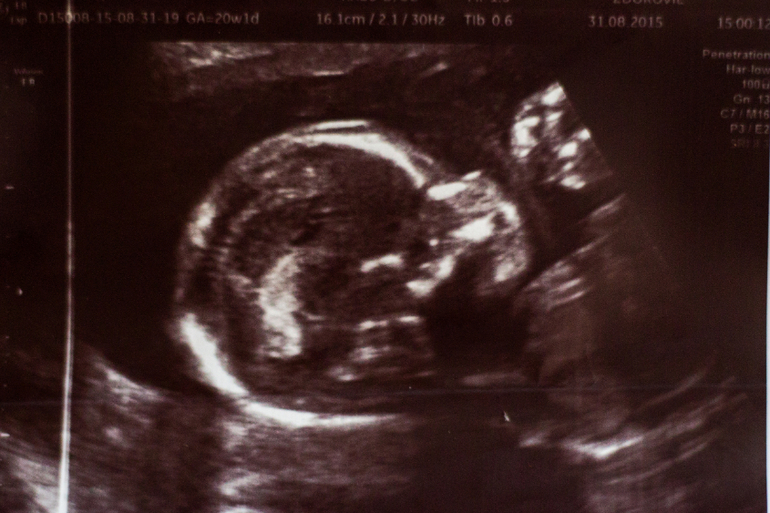

ЭкваторВ воскресенье у нас было ровно 20 и в понедельник на 20 и 1 мы ходили на второй скрининг всей семьей. Я только на кушетку легла, только картинка на мониторе появилась, доктор сразу говорит: у вас МАЛЬЧИК))))))) И на мониторе достоинство крупным планом))

По УЗИ все хорошо. Самое главное что у него нет кист в почках, боялась что от меня достанутся. И шейка 40 мм и закрытая, но следить нужно продолжать, т.к. в первую бер на 26 нед была уже 25 мм и палец пропускала.

Ну и в заключение фотопуз на 20 ровно, фотоУЗИ малыша и опрос для статистики:

Даже в УЗИ протоколе прописано что плод мужского пола)) Так что смело можно покупать коляску мальчуковой расцветки)) Перебрать вещички старшего и докупить что-то для нашего второго мальчишки)))